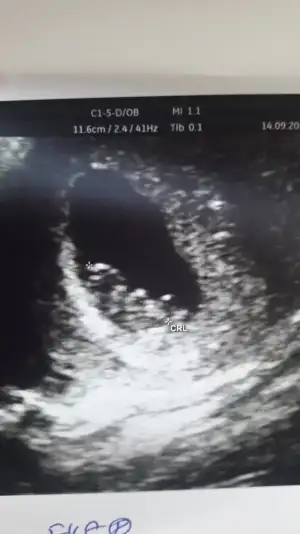

Kızlar bende nisanda doğumum olacak inşallah 10+3 tahmin alabilirmiyim

Eklentiler

• image.webp

image.webp

27,6 KB · Görüntüleme: 75